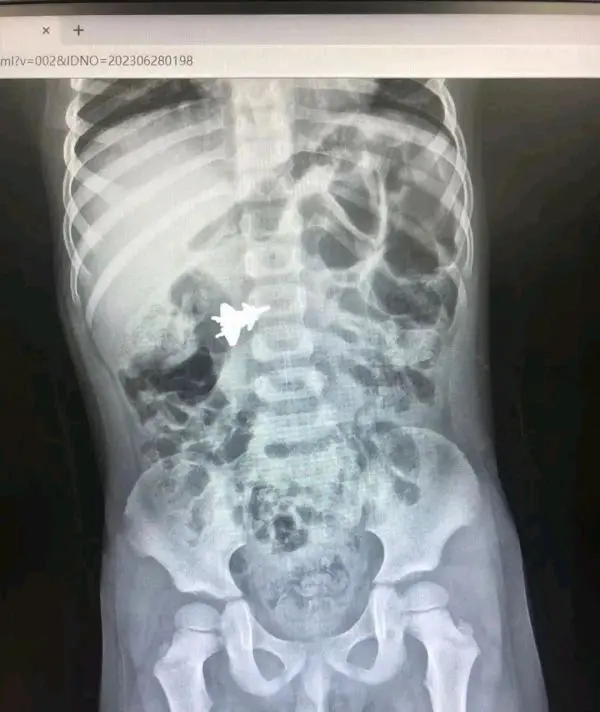

广西4岁男孩吞下“歼-20”!拍片可见飞机在肚子里“飞”……

6月28日,南宁4岁男孩小明(化名),因误吞金属玩具飞机,被紧急送往广西医科大学第一附属医院救治。 据了解,孩子吞下的玩具飞机是一架歼-20模型,为金属材质,长约3厘米。事发当天早上,小明拿着飞机模型在嘴边玩,玩着玩着打了个喷嚏,不小心把模型吞入肚子。

广西医科大学第一附属医院小儿外科副主任医师李伟说 :“这个飞机模型有翅膀,所以还是有一定的尖锐度。我们采取了一些吃流质、口服石蜡油的措施,观察飞机模型在孩子的肚子里面的轨迹。 ”与此同时,医生还定期复查拍片,了解飞机模型在体内的运动轨迹。医师团队通过连续几次腹部立位片看到,飞机模型先在幽门“盘旋”,然后“飞”到空肠、回肠,再进入到回盲部的最后关卡。两天后,飞机模型终于成功经肛门排出。 医生提醒,异物吞食在学龄前期时常发生,异物因大小、形状不同、性质不同可能造成不同的伤害,如消化道穿孔、出血、化学物质灼伤等危险情况,严重的可能会危及生命。暑期来临,家长要多教授孩子们安全知识,谨防吞食异物。一些低龄孩子吞食异物后不会表达,家长若观察到孩子有腹痛、头痛、发烧、血便、呕吐等异样,应及时送医处理。